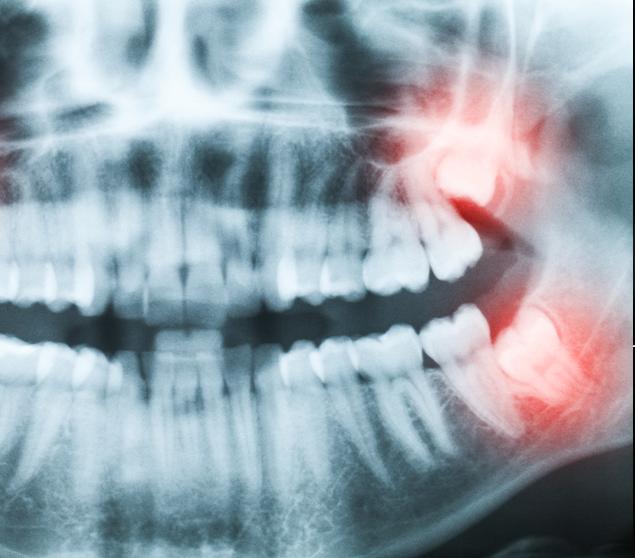

Before recommending extraction, our dental team completes a thorough assessment, which may include a clinical examination and dental X-rays. Findings and treatment options are reviewed clearly so you can make informed decisions about your care.